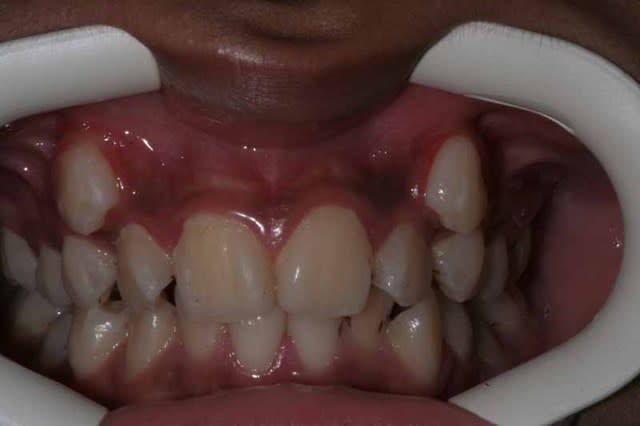

Vous vous rappelez de ce cas Damon ?

Image 1 qf9ljh - Eugenol

14 mois séparent les photos.

@+ Bjc.